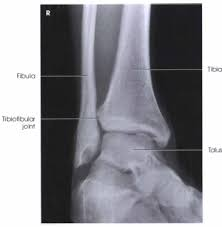

Mortise ankle structures best demonstrated

Ankle mortise joint space open between medial and lateral malleoli.

Minimal superimposition at the distal tibiofibular joint.

The mortise joint refers to the space formed by

• Medial malleolus

• Lateral malleolus

• Talus between them.